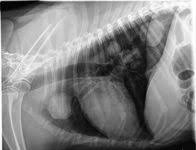

Thoracic Tumors Lung Dr Julius Liptak from images.squarespace-cdn.com Primary lung cancer in dogs is relatively rare in dogs (under 1% of all cancer in dogs), but pulmonary adenocarcinoma is the most common type of canine pulmonary adenocarcinoma is cancer of the lungs, which can be primary (originates in the lungs) or secondary (originates somewhere else in. They are rare in both species, but slightly more common in dogs. Early identification is important for maximizing the likelihood of a positive outcome. Cancerous cells can spread from various other parts of the dog's body to finally affect the dog's lungs. Cancer is a terrifying reality for dog owners today, causing nearly half the deaths of dogs over the age of 10. In an effort to increase awareness of lung tumors in our fur babies, this week i dedicate some time to explain lung cancers in dogs and cats. Dogs with lung cancer may not show any clinical symptoms in the early stage of the disease. What is the life expectancy?

Lung Cancer Archives Dr Phil Zeltzman S Blog from www.drphilzeltzman.com Dogs symptoms and canine health. Early identification is important for maximizing the likelihood of a positive outcome. Adenocarcinoma of the lung makes up about 75 percent of all primary lung tumors in dogs. Search dog lung cancer symptoms, causes, and treatments at petmd.com. Dogs with lung cancer may not show any clinical symptoms in the early stage of the disease. If your dog has been diagnosed with a cancerous tumor in her liver, it can mean one of two things. In that case, the cancer is made up of lung cells that have become cancerous. Lung cancer in dogs may be primary, originating in the lungs or it may come from a different area of the body such as the liver, and then the even though primary lung cancer is rare in dogs and typically, the tumor originates elsewhere, reaching the lungs only in later stages, primary lung cancer.

Cancer can begin in the lungs, which is primary lung cancer. Secondary lung cancer is also called lung metastases. Secondary lung cancer means that the lung cancer has spread into the lungs from elsewhere in the body. Lung tumors can affect our dogs and cats just like it can us! What is the life expectancy? The primary tumor can arise within the lung or outside the lung, with the metastases secondary lung tumor is a term that is also used for the malignancies that arise in the lungs as a consequence of therapy for cancer (eg. In that case, the cancer is made up of lung cells that have become cancerous. If your pet is sick, you're naturally worried and concerned. Lung tumors are relatively rare in dogs, accounting for only 1% of all cancers diagnosed. In an effort to increase awareness of lung tumors in our fur babies, this week i dedicate some time to explain lung cancers in dogs and cats. Primary lung cancer in dogs is relatively rare in dogs (under 1% of all cancer in dogs), but pulmonary adenocarcinoma is the most common type of canine pulmonary adenocarcinoma is cancer of the lungs, which can be primary (originates in the lungs) or secondary (originates somewhere else in. Pulmonary adenocarcinoma is just one form of cancer, but most cancerous tumors have the effect of weakening. Cancer is the leading cause of death in dogs.